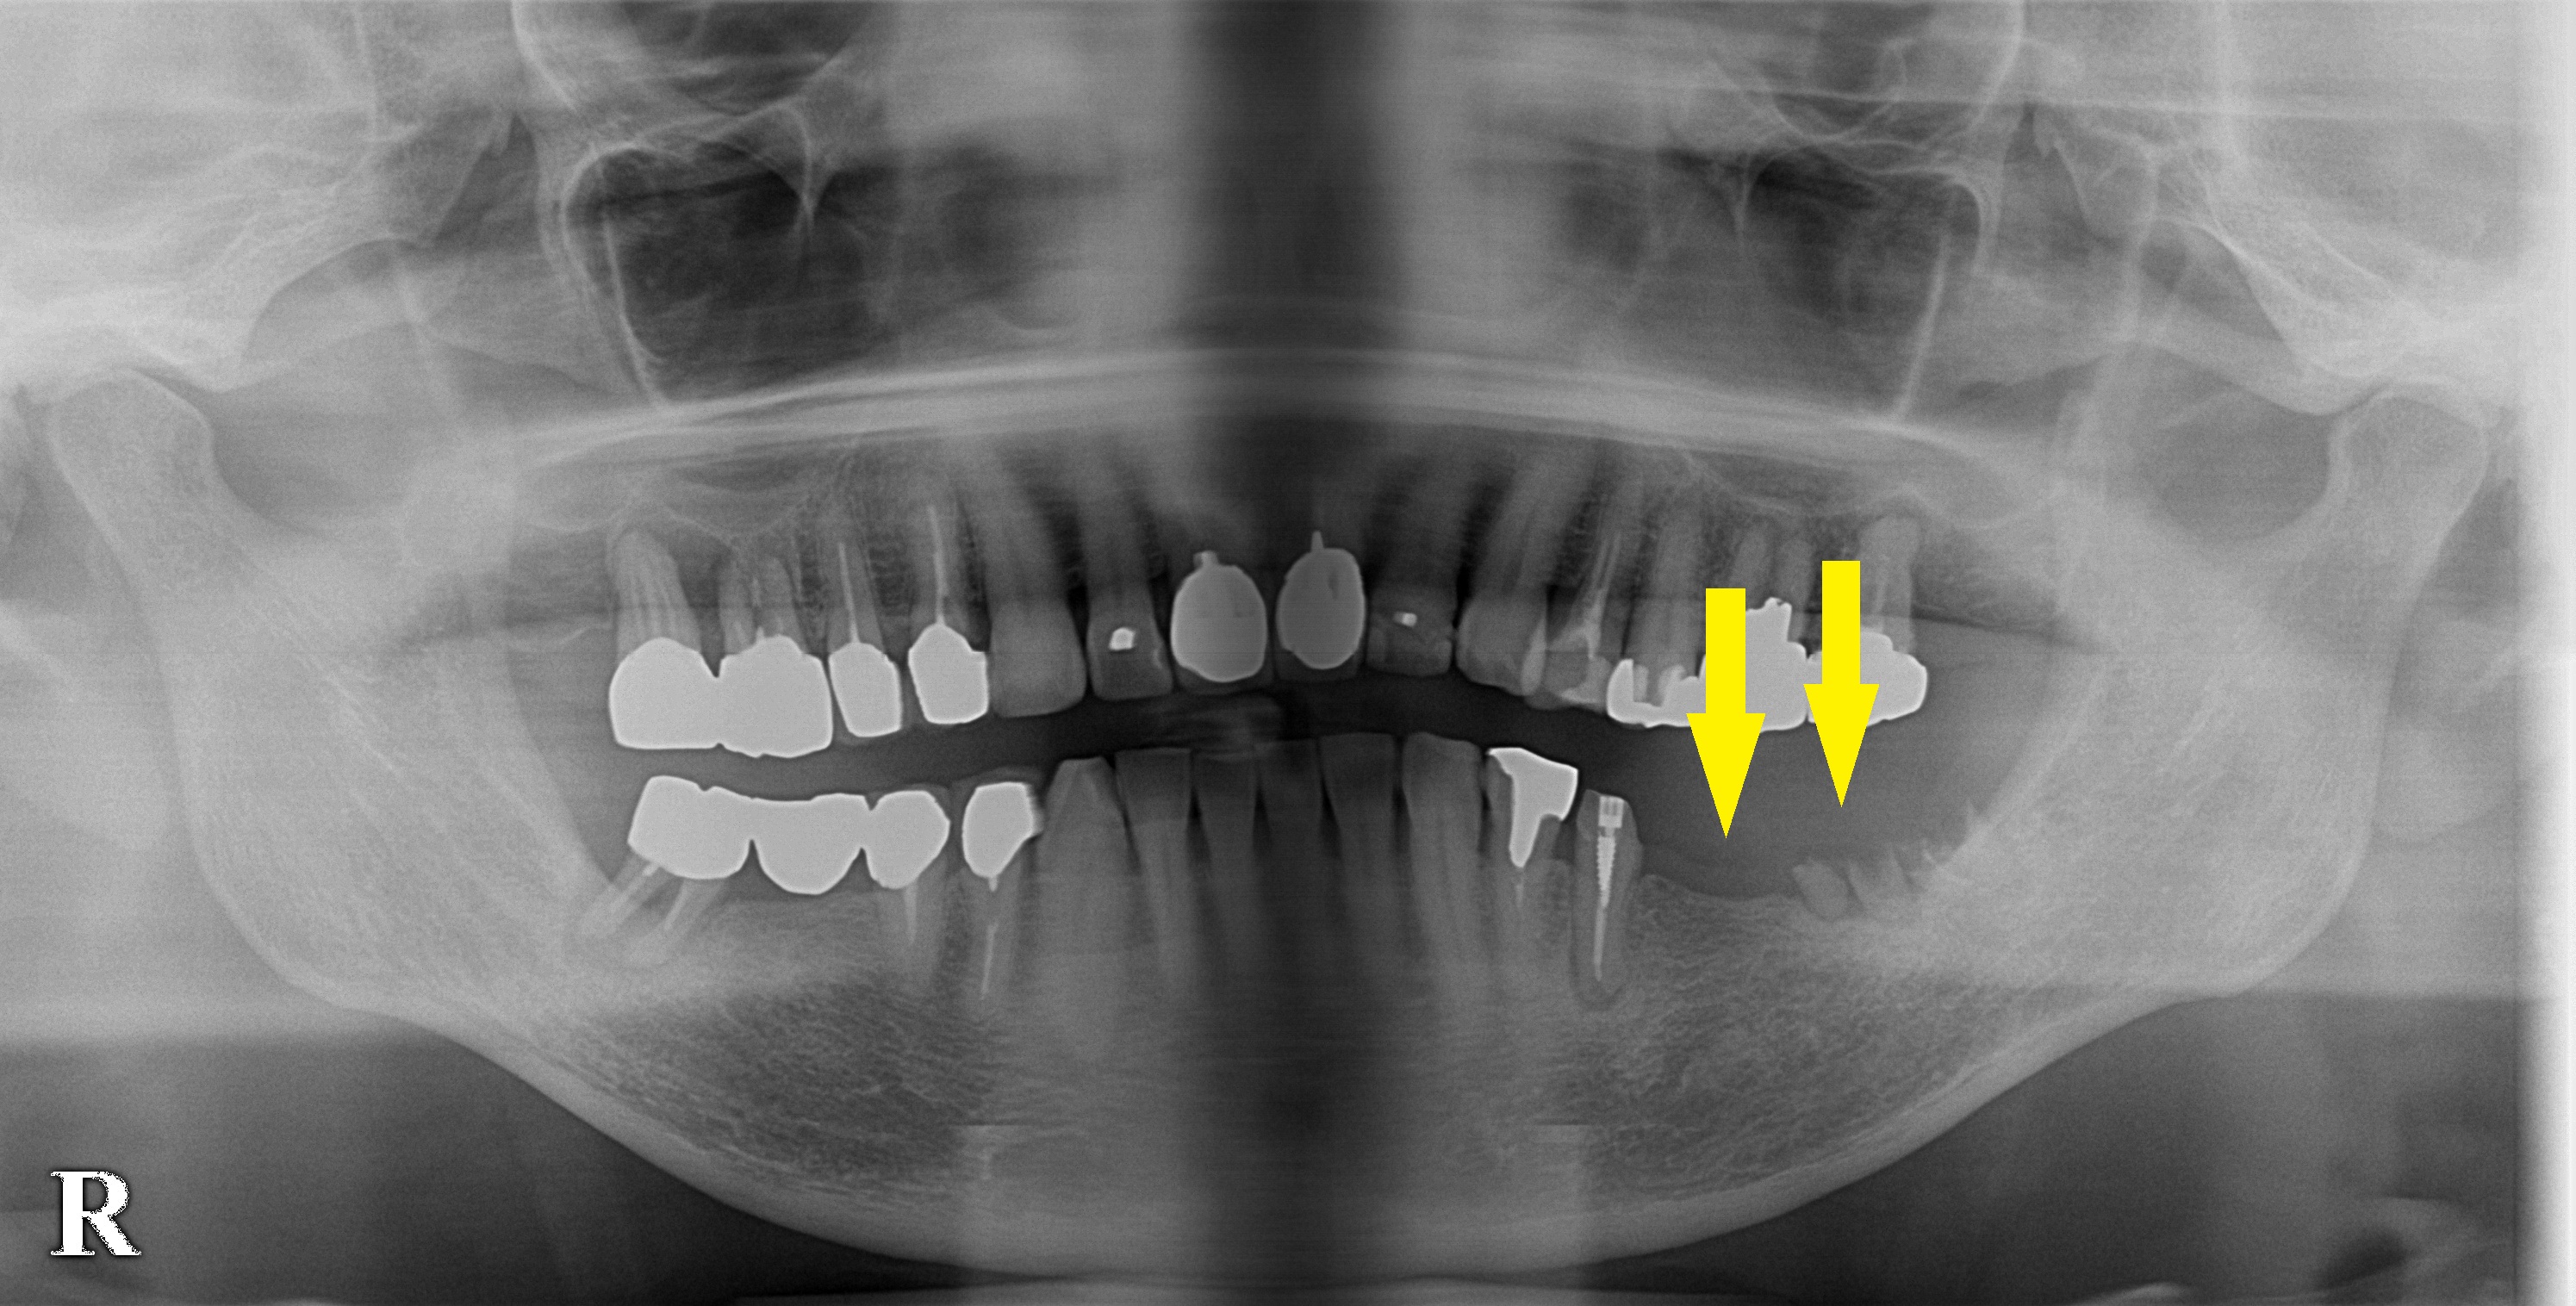

左下顎にブリッジが入っていたそうですが、支えになっている後方の歯がボロボロになり外れてしまったそうです。

来院された時には、大臼歯がわずかに、残根の状態で残っているだけでした。

後方に歯がないために、ブリッジはもう不可能ですので、入れ歯かインプラントということになります。

インプラント治療を希望されましたので、残根状の歯は抜歯、左下顎大臼歯部に、本日2本のインプラント埋入術を行いました。